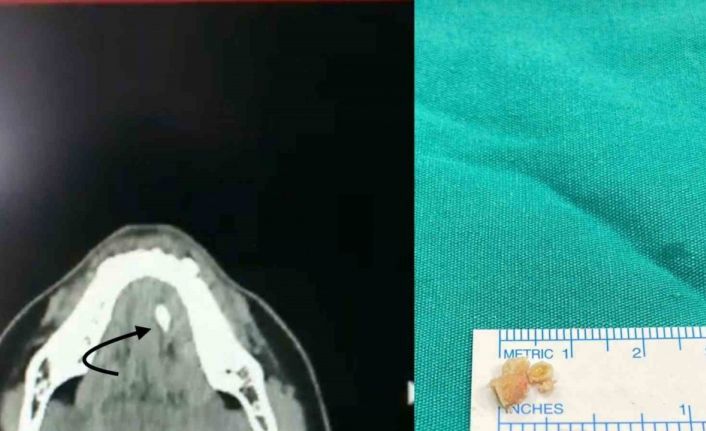

Şikâyetleri daha hafif olan ve taş boyutları küçük ve tükürük bezi kanalının ucuna yakın yerde yerleşim gösteren hastalarda geleneksel tedaviler önerildiğini dile getiren Doç. Dr. Nesrettin Fatih Turgut, “Ağrı kesiciler fayda sağlar. Bol sıvı tüketimi, ısı uygulaması rahatlama sağlayabilir, bol sıvı tüketimini tüm hastalarımızda önermekteyiz. Aynı zamanda limon gibi ekşi ürünlerin emilmesi tükürük sıvısını artırır ve çok küçük taşların dışarı atılmasını sağlayabilir. Taş boyutunun büyük olması, taşında daha çok beze yakın yerde yerleşmiş olması durumlarında ise cerrahi uygulamaları gündeme gelmektedir. Taş yerleşimi, büyüklüğü etkilenen tükürük bezinin durumu cerrahinin şeklini belirler. Eğer taş tükürük bezi kanalında yer alıyorsa, sialendoskopi olarak adlandırılan kamera sistemi ile yer tespiti ve çıkarma işlemi herhangi bir kesi olmaksızın tercih edilir. Ancak taşın tükürük bezi içerisinde yer alması, boyutunun çok büyük olması durumlarında ise dışardan veya ağız içinden yaklaşım ile cerrahi seçenekleri gündeme gelmektedir” diye konuştu.

Tükürük bezi kanallarının içindeki en uç bölgelere kadar ulaşabilen bir kamera sistemini kullanarak tükürük kanallarını inceleme yöntemi olan sialendoskopiden bahseden Doç. Dr. Turgut, “Bu sistem, kanal içindeki hastalıkların tanısı ve tedavisi için bir araç sağlar. Kamera sisteminin temel özelliği, tükürük kanalının içini milimetrik boyutlarda kontrol etme yeteneğidir, yaklaşık 1.5 mm’lik bir boyuttan bahsedilmektedir. Bu işlem genel anestezi veya lokal anestezi altında uygulanabilir. Hekimin deneyimi, hastanın sağlık durumu, hastanın uyumuna ve tercihine bağlı olarak tedavi planlaması yapılır. Sialendoskopi, genellikle tükürük kanallarında taş olan hastaların tedavisinde kullanılmaktadır. Ayrıca Sjögren hastalığı, radyoaktif iyot tedavisi almış hastalar ve tekrarlayan tükürük bezi iltihaplarına sahip çocuk hastalarda da bu yöntem uygulanabilir. Sialendoskopi süresi, taşın büyüklüğü ve konumuna bağlı olarak değişebilir. Büyük taşlar havalı kırma tekniği kullanılarak küçültülerek çıkarılır, bu nedenle işlem süresi uzun olabilir. Sialendoskopi sırasında herhangi bir kesi veya dikiş uygulanmaz, bu nedenle işlem sonrasında ağrı veya şikâyet gözlemlenmez. Geçici olarak aynı taraftaki tükürük bezinde şişlik olabilir ancak genellikle bu şişlik 1-2 saat içinde azalır. Hastalar, genellikle aynı gün içinde taburcu edilirler” şeklinde konuştu.

Cerrahi müdahale seçeneği hakkında da bilgi veren Turgut, “Taş boyutunun büyük olması, taşın bez içinde yerleşim göstermesi, sık enfeksiyona bağlı taşın kanala yapışık olması gibi nedenlerden dolayı sialendoskopi ile taşın çıkarılması mümkün olmayabilir. Bu durumlarda açık cerrahi seçeneği gündeme gelir. Eğer taş, kanal içinde yerleşim gösteriyorsa ağız içerisinden kanal üzerinde yapılacak ufak bir kesi ile taşa ulaşılır ve taş çıkarılır. Birkaç dikiş atılarak işlem tamamlanır. Hastalarımız ancak taş tükürük bezi içinde olursa veya tükürük bezi sürekli (kronik) enfeksiyona bağlı olarak işlevini yitirmişse (atrofiye uğramış) tükürük bezi genel anestezi altında çene altından kesi yapılarak tamamen çıkarılır. Ameliyat sonrası 2-3 gün hastane yatışı gerekebilir” ifadelerini kullandı.